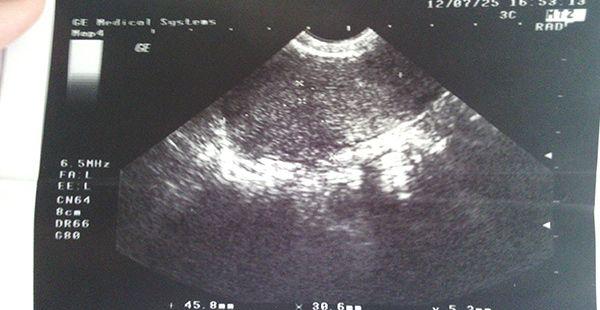

B超是一项通过超声波传递途经的一项检查,是一种非手术的诊断性检查,在临床上多有运用,可以让患者在无痛、无损伤的情况下放心接受检查。虽说这项检查很方便,但对于一些人而言,也是头一次做,那么接下来本文就向大家介绍相关的流程攻略。

B超是一种超声波检查